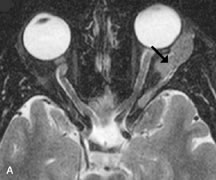

MRI and MRV are more sensitive than CT in revealing cavernous sinus thrombosis. Engorgement of the cavernous sinus, extraocular muscles, and ophthalmic veins is seen with hyperintensity of the thrombosed sinuses evident on all pulse sequences. The enlarged, thrombosed superior ophthalmic vein appears less hypointense than the normal contralateral ophthalmic vein, and hyperintensity within the lumen of the vessel may be seen on T1- and T2-weighted MR images.68